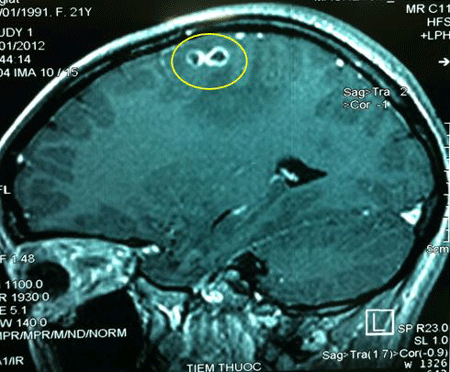

_ Dấu hiệu khi nhiễm sán heo là khi trẻ đi tiêu, sán sẽ tự đi ra theo đường phân hoặc trẻ bị sụt cân, suy dinh dưỡng. Trường hợp nguy hiểm hơn, sán lợn có thể "lạc" lên não làm trẻ co giật, hôn mê, nổi sần trên da thì nên đưa trẻ đến bệnh viện thăm khám và xét nghiệm.

_ Thông thường, bệnh nhân có dấu hiệu ký sinh trùng xuất hiện ở da như nổi sần, hôn mê, co giật, yếu liệt chi... Bác sĩ nghi ngờ do ký sinh trùng hoặc những bệnh lý liên quan khác đều cho xét nghiệm tìm ký sinh trùng.